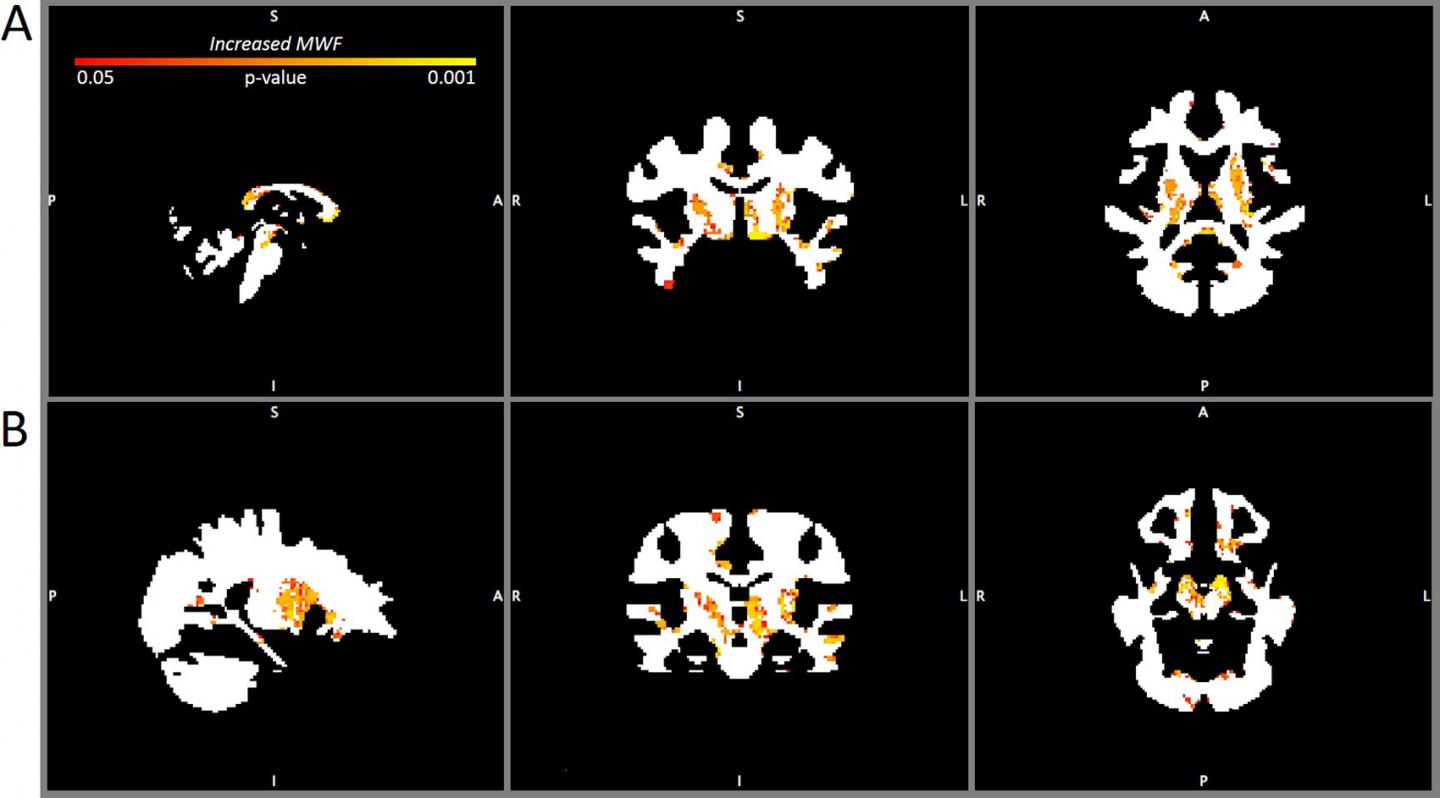

image: MWF maps comparing the brains of contact sport players 3 months after mild traumatic brain injury with the non-contact sport player baseline. A: Sagittal (left), coronal (center), and axial (right) MWF maps at the level of the thalamus showing increased MWF (p right temporal lobe).

These findings are depicted on MWF maps, essentially anatomical masks of white matter over which colored areas show an increased or a decreased MWF.

The increased MWF after mild TBI found in this study demonstrates an active remyelination process after mild TBI. However, as the researchers point out, increased myelin alone is not necessarily a good thing. Animal studies have shown that remyelination following mild TBI may result in disorganized and therefore less functional myelin.

In a related investigation, the researchers compared MWF maps obtained in this study with PET scans obtained in patients suspected of having CTE. The researchers found that the sites of increased MWF in CSPs at both time points corresponded to sites of brain changes in patients suspected of having CTE.